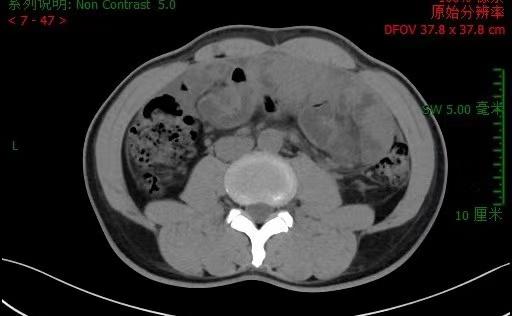

图说: 李先生入院腹部CT 采访对象供图(下同)持续腹痛,进食梗阻1年,“元凶”竟是肚子里长了一个“茧”!近日,上海交通大学医学院附属仁济医院刘颖斌团队为一名罕见“腹茧症”患者李先生(化名)抽“...

刘颖斌(右)与高钢龙(左)在手术中持续腹痛,进食梗阻1年,“元凶”竟是肚子里长了一个“茧”!近日,在上海交通大学医学院附属仁济医院刘颖斌团队为一名罕见“腹茧症”患者(化名李先生)抽“丝”剥“茧”...